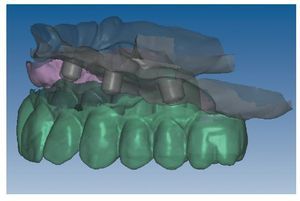

Mediante el uso de un escáner óptico de luz estructurada, los protocolos CAD registran los primeros datos relativos al modelo maestro con las correspondientes posiciones de implante (figs. 87 y 92). En el siguiente paso tiene lugar la digitalización de la planificación, previamente realizada en cera de escaneo matificada, de la restauración definitiva (figs. 88, 90 y 93). La subsiguiente conciliación de los datos mediante el uso del software de diseño dental permite al protésico planificar virtualmente el resto del procedimiento (figs. 89 y 91, 94 a 96) a partir del diseño de las estructuras (figs. 97 y 98).

Fig. 87. Imagen CAD del modelo maestro superior.

Fig. 88. Imagen CAD de la planificación definitiva para el maxilar superior.

Fig. 89. Planificación CAD de la estructura del maxilar superior.

Fig. 90. La posición de los implantes en relación con la planificación.

Fig. 91. El diseño definitivo de la estructura para el maxilar superior.